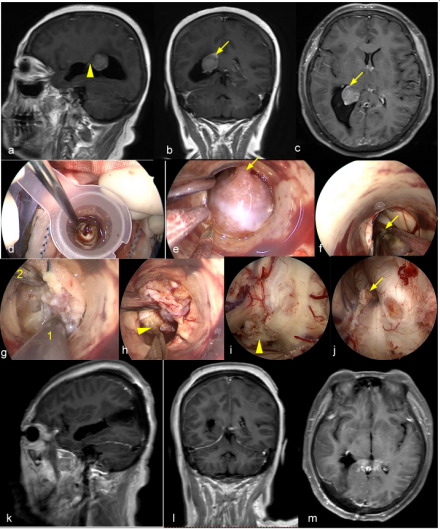

图1. A-C 向蝶鞍下方发展的侵袭骨质的垂体腺瘤。A、C 术前、术后轴位T1增强MRI。B术中所见,向侧下方磨除被肿瘤侵袭的颈静脉结节骨质。D-L 广泛侵袭颅底的垂体腺瘤。D、F术前、术后1年矢状位T1增强MRI。E 术中骨窗显露范围。G 肿瘤切除后正常垂体予以保留。H 肿瘤切除后第三脑室开放。I肿瘤切除后显露额叶及前交通动脉复合体。K 斜坡后方肿瘤切除后显露脑干及桥前池。J、L术前、术后1年冠状位T1增强MRI。1斜坡;2右侧视神经管;3视神经管-颈内动脉隐窝;4蝶骨平台硬膜;5鞍结节硬膜;6 鞍底硬膜;7斜坡硬膜;8 斜坡旁段颈内动脉;9第三脑室;10 垂体柄;11额叶直回;12 前交通动脉复合体;13脑干;14基底动脉;15左侧外展神经。黄色箭头所示为被肿瘤侵袭的颈静脉结节;无尾黄色箭头所示为正常垂体。

图11. 内镜经Endoport切除侧脑室三角区脑膜瘤。a-c 术前增强MRI可见左侧脑室三角区脑膜瘤。D逐渐扩张通道置入Endoport;e向前方探查确认肿瘤起源的脉络丛;f电灼肿瘤起源的脉络丛;g肿瘤质地硬韧,应用超吸快速减容;h肿瘤减容后探查肿瘤下极,电灼并切断与脉络丛的粘连;i肿瘤切除、创面止血后水环境下观察,可见向侧脑室颞角方向延伸的脉络丛;j向侧脑室房部延伸的脉络丛。j-l术后增强MRI可见肿瘤全切。箭头所示为肿瘤上方向侧脑室房部延伸的脉络丛;无尾箭头所示为肿瘤下方向侧脑室颞角延伸的脉络丛;1吸引器;2超吸刀头。